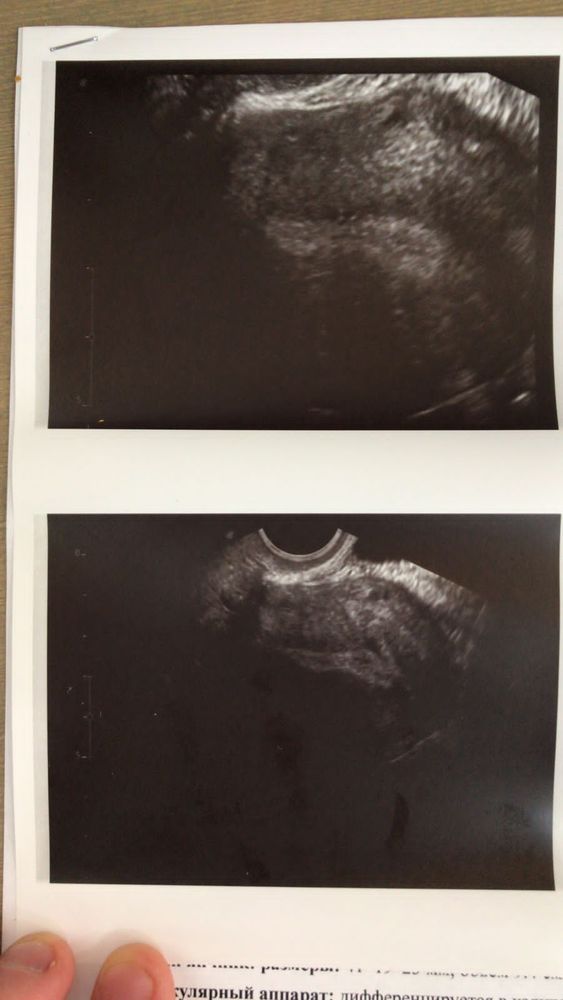

Сдала анализы. Пока жду результаты нашла другого узиста. Прихожу она спрашивает все, все жалобы, тогда пришел уже амг, высокий. Верхняя граница 7, а у меня больше 12. Смотрит яичники все говорит вроде неплохо, идет дальше и тут резко замолкает, нахмуривается и до самого конца приема не говорит ни слова, очень долго смотрит, морщится, снова смотрит и молчит.. Сказать, что я испугалась? Я вылетела от нее, и не разворачивала заключение пока в машину не села. Куча неизвестных слов. Гуглить всю ночь мне🙈 нагуглила, но все равно куча вопросов.

Фотал муж😁

Я не врач и не узист, но по снимкам и что смогла в инете найти прям не нравится мне внутренний вид моей матки совсем....